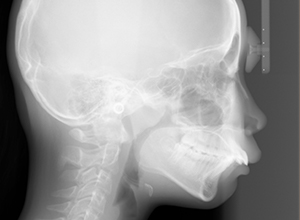

X-Ray

X-Ray所見

セファロ所見 下顎骨はしっかりとしているが顎顔面の奥行きに比べて下顔面高さが低い。頭蓋に対して上顎骨は前方位にあり、上下顎骨の前後的位置関係のズレは大きかった。